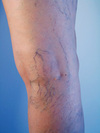

Grey turner’s

Flank ecchymoses

Grey Turner’s sign

Flank ecchymosis